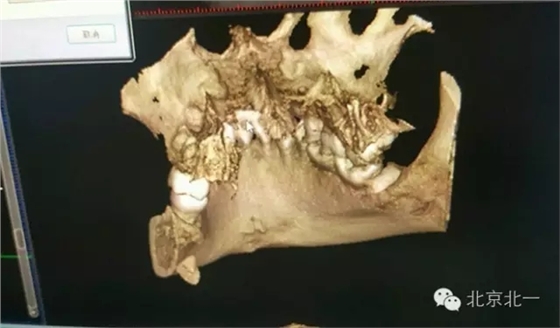

圖二:CBCT重建可見牙根位于舌側(cè)達(dá)到頜下間隙。